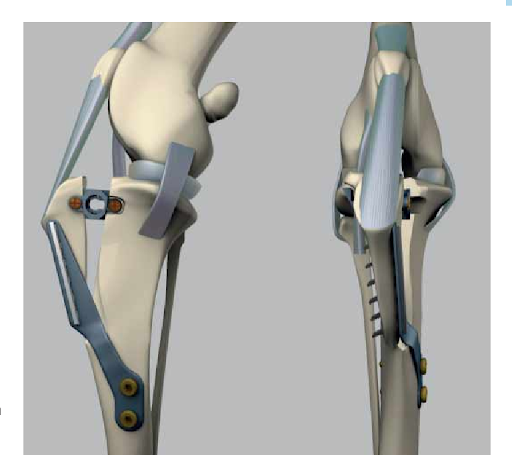

- Tibial tuberosity transposition (TTT)

- This procedure involves using a metal rod, wires and creating a bone fragment to create stability in the knee ligaments and tendons to hold the kneecap in its natural position (Figure 3).

Figure 3: Tibial tuberosity transposition diagram (Yeadon 2010, https://www.semanticscholar.org/paper/Tibial-tuberosity-transposition-advancement-for-of-Yeadon-Fitzpatrick/6d3b71278a5ebcc1d85fa99bafd91cacf10ed548)